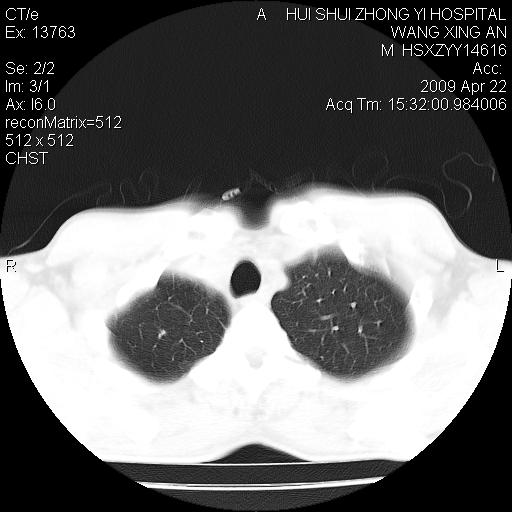

标题: CT19534:患者男、46岁咳嗽、胸痛半月。 [打印本页]

标题: CT19534:患者男、46岁咳嗽、胸痛半月。

1、右下肺中央型肺癌并右肺转移,右肺下叶不张。(肿块围绕右肺下叶支气管生长,致管腔闭塞右肺下叶不张;右肺有结节影)。

2、右侧胸腔积液。

3、右中上肺陈旧性肺结核(右肺见纤维化病灶及点状钙化)。